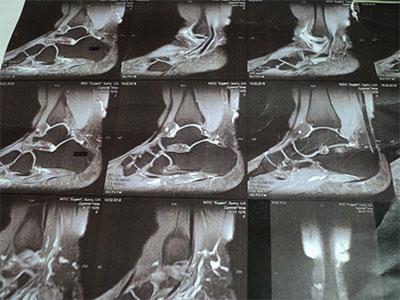

- Методы диагностики: Кроме УЗИ и МРТ, могут быть также использованы рентгенография и анализы крови для выявления воспалительных маркеров.

Главные симптомы включают боль, отечность и изменение цвета кожи в области сустава. Воспалительный процесс приводит к нарушению функций ноги, что проявляется хромотой. Для подтверждения диагноза требуется дополнительные исследования – рентгенография, УЗИ, пункция сустава, МРТ.

Диагностика в ЦМРТ

Чтобы точно определить форму синовита и его происхождение, одного визуального осмотра недостаточно. В ЦМРТ применяют современныедиагностики methods:

- компьютерная томография (КТ) сустава;

- ультразвуковое исследование (УЗИ);

- анализы крови и мочи;

- артроскопия по показаниям.

Комплексная диагностика в ЦМРТ позволяет точно выявить воспалительный процесс и подобрать индивидуальные методы лечения.

Диагностика заболевания

Лечение синовита голеностопного сустава начинается лишь после того, как диагноз будет подтвержден. Для этого применяют следующие методы диагностики:

При значительном отеке тканей провести оценку состояния сустава бывает непросто, поэтому может потребоваться дополнительно УЗИ, МРТ или рентгенографическое исследование.

Инструментальные методы